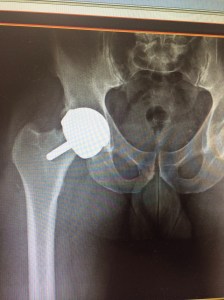

My hip resurfacing has failed. So back in for a revision. June 4th 2015